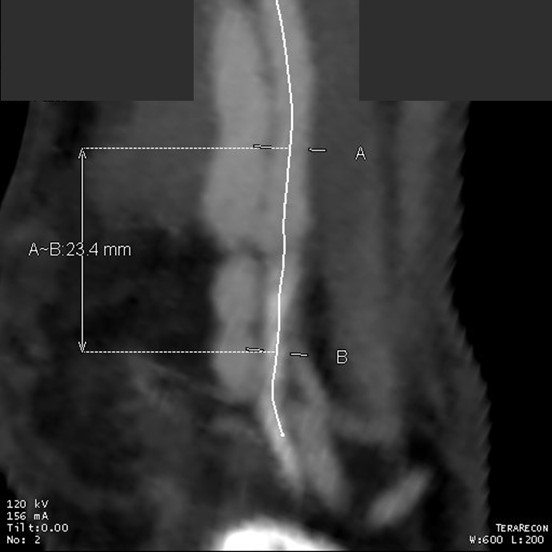

Patient is a middle aged man with history of DVT and PE who in preoperative workup for another operation was found to have a popliteal venous aneurysm affecting his right leg. Unlike the recently posted case (link) which was fusiform, this aneurysm was saccular (CT above, duplex below). Popliteal venous aneurysms have a high risk of pulmonary embolism because: they tend to form clot in areas of sluggish flow and once loaded with clot, will eject it when compressed during knee flexion.

In fact, I use these images to plan open surgery, even to the location of incisions. Vital structures are seen in 3D and injuries are avoided. Take for example the CT Venogram on the panel below. By adjusting the window level, you have first the venographic information showing the saccular popliteal venous aneurysm on the left panel, you can also see where it is in reference to the muscles in the popliteal fossa. The greater saphenous vein and varicose veins below are well seen.